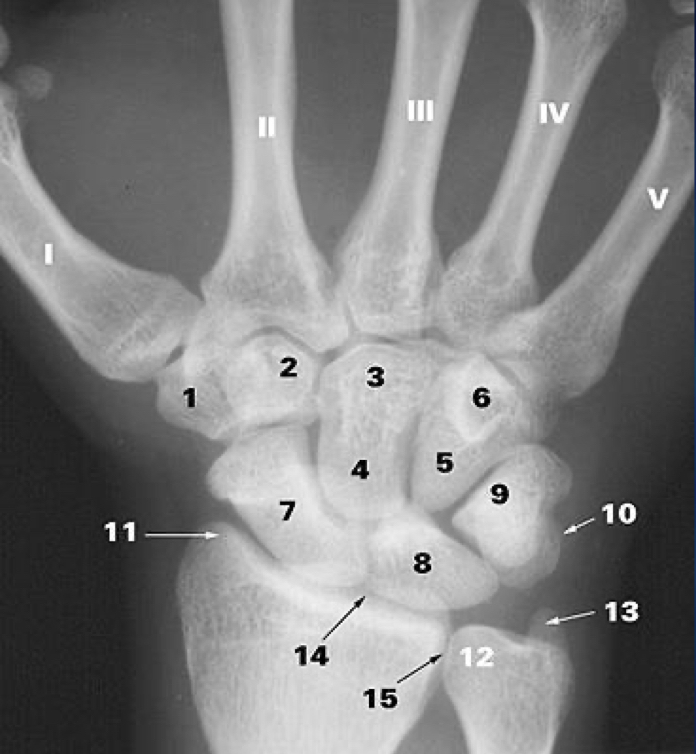

1

trapezium b.

2

trapezoid b.

3

capitate b.

4

hamate b.

5

hook of hamate

6

scaphoid b.

7

lunate b.

8

triquetrum b.

9

pisiform

10

styloid process of the radius

11

head of the ulna

12

styloid process of ulna